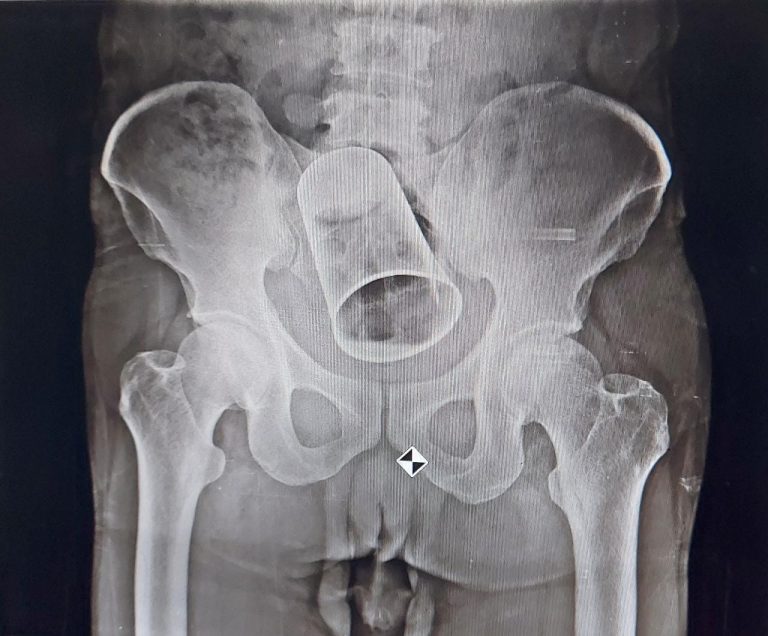

During consultation, he revealed the incident to the doctors. After finding the glass stuck in the intestine in X-Ray report, the doctors tried to retrieve the glass through rectum. After failing in their efforts, they advised him to go for surgery.